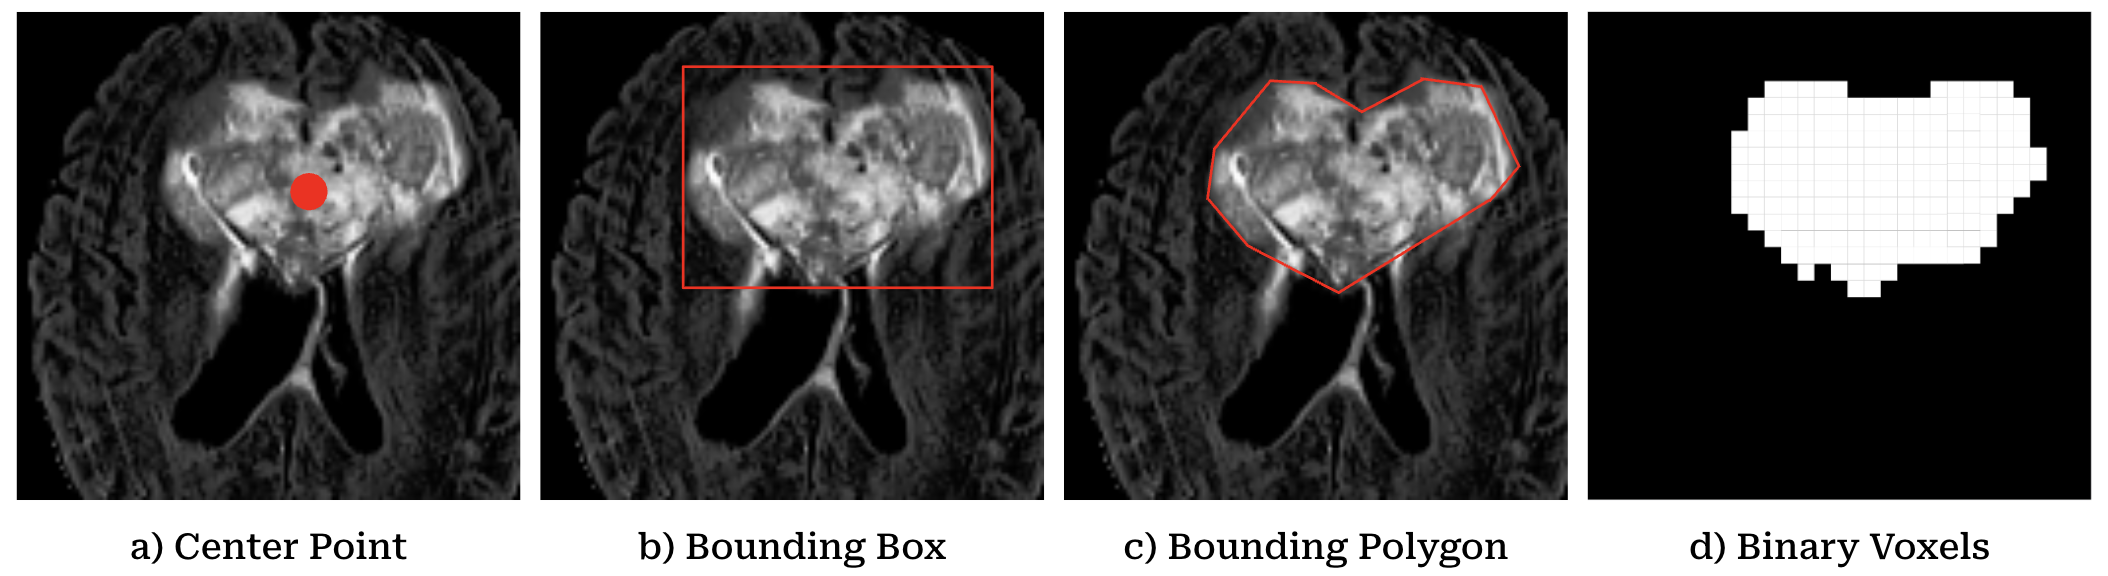

For the segmentation tasks, each of the 365 patients had a 95x128x128 scan structured as a voxel occupancy grid, where zero values indicated regions without glioma and non-zero values represented glioma presence. To ensure viable segmentation, the first and last slices containing glioma were identified in the axial, coronal, and sagittal planes, allowing for the exclusion of non-glioma slices, ensuring that only relevant slices were used in training, thus minimizing potential confusion. Three types of segmentation data were extracted. The first method involved defining a bounding box for each axial slice containing glioma. This was done by extracting the minimum and maximum coordinates along both the x and y axes (xmin, xmax, ymin, ymax), creating a square bounding box. The bounding box was represented by four points: top-left, top-right, bottom-right, and bottom-left, stored in a (4, 2) array for each slice. The second approach focused on the center of the glioma, where the center of the bounding box was calculated and recorded as a single (1, 2) coordinate for each axial slice containing glioma. This representation was simpler but still provided the important information on glioma localization. The third, most complex approach involved representing the glioma with polygons. For each axial slice, the boundary of the glioma was traced using 10 to 15 points, following a clockwise direction starting from the north-most point. Smaller gliomas used fewer points, while larger or more irregularly shaped ones used more. The polygon data was stored as a list of coordinates with shape (10-15, 2), capturing the detailed contours of the glioma. This method offered the most precise and detailed segmentation, providing data for training segmentation models with a higher degree of accuracy in tumor shape and location.

Refer to caption

Figure 3: Sample segmentations using a) center points, b) bounding boxes, c) bounding polygons, and d) the given form of binary voxels.